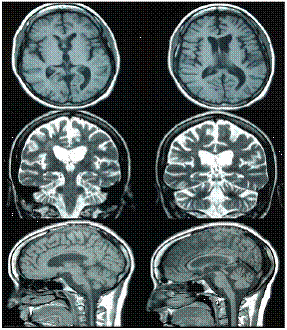

Se iniciaron, entonces, la terapia de rehabilitación neuropsicológica para el déficit cognitivo y la terapia fonoaudiológica centrada en el habla y el lenguaje, y se continuó con las fisioterapias motora y sensorial de soporte. En las sesiones de rehabilitación neuropsicológica, se emplearon rehabilitación viso-espacial, la terapia cognitivo-lingüística, corrección de apraxias, y entrenamiento de la memoria y las habilidades de atención. En la figura 2 se presenta la resonancia magnética de seguimiento.

En el examen físico de la paciente, realizado seis años después del accidente, los especialistas en rehabilitación neurológica reportaron una persona consciente, orientada en las tres esferas, con lenguaje comprensivo y coherente. En la evaluación cognitiva de Montreal (Montreal Cognitive Assessment, MoCA) su puntaje fue de 25. Presentaba integridad de los 12 nervios craneales, una leve alteración en la marcha, con dificultad para la movilidad de la extremidad inferior izquierda, aunque sin necesidad de apoyo para caminar, una fuerza de 5/5 en las extremidades superiores y de 4+/5 en las inferiores, así como coordinación, sensibilidad y tono normales, reflejo rotuliano exaltado, reacción plantar neutra bilateral y el fijador de Hoffman se había retirado. La paciente presentaba clonus agotable en la extremidad inferior izquierda, y ya había logrado terminar una carrera tecnológica.

Ocho años después del accidente la paciente fue sometida a evaluaciones de neurología clínica y rehabilitación neurológica, y los resultados indicaron que tenía autonomía para las actividades básicas, aunque requería ayuda para algunas actividades instrumentales (por ejemplo, manejar el computador). Hoy trabaja en el negocio familiar. Su puntaje en el Mini- Mental State Examination es de 29 sobre 30, y de 26 en el MoCA. Persistía un defecto pupilar aferente en el ojo derecho por atrofia óptica de predominio derecho, y su agudeza visual de lejos en el ojo derecho era de 20/400 y de 20/80 con corrección en el izquierdo. Su fuerza en miembros inferiores continuaba siendo de 4+/5 (paraparesia espástica leve de predominio izquierdo), y presentaba hiperreflexia rotuliana y clonus agotable en el pie izquierdo, pero sin temblor en acción ni en reposo. Su coordinación bimanual era normal y no tenía contracturas musculares ni patrón flexor en las extremidades. La paciente lograba caminar en puntas y talones, presentaba taquilalia y disartria central moderadas y, a nivel cognitivo, predominaba una amnesia anterógrada de evocación de la información y un trastorno de leve a moderado de la función ejecutiva.